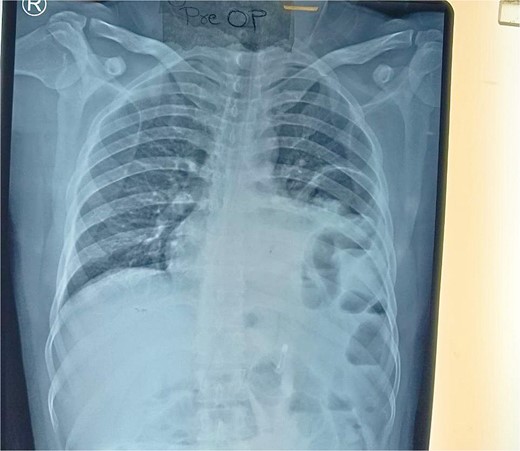

Routine examinations, including total blood counts, differential blood counts, renal function tests, and liver function tests, were within normal limits. The chest X-ray PA view showed the herniation of bowel loops into the left hemithorax with the collapse of the lower zone of the lung with no evidence of previous fracture (Fig. 1). Computed tomography (CT) showed a defect of size around 4 cm with evidence of protrusion of intra-abdominal content in the left hemidiaphragm with basal atelectasis of the left lung and mild dilatation of the jejunal bowel loops with a few air-fluid levels without a transition point (Fig. 2). The patient underwent laparoscopic left diaphragmatic hernia repair with mesh hernioplasty after 6 h of admission. The intraoperative findings revealed a defect of size 4 cm × 2 cm at the posterolateral aspect of the left hemidiaphragm with protrusion of the transverse colon, omentum, and part of the spleen with adhesions (Fig. 3). The content of the hernia was reduced, and primary repair of the defect was done (Fig. 4), and the defect was closed with a 10 × 15 cm intraperitoneal onlay composite mesh (Fig. 5). A postoperative X-ray showed no evidence of herniation of the bowel loops above the left hemidiaphragm (Fig. 6). He was discharged on the fourth postoperative day with oral medications. Follow-up in the outpatient department on the 14th postoperative day showed that he was doing well.

Chest X-ray PA view showing the herniation of bowel loops into the left hemithorax with collapse of the lower zone of the lung.